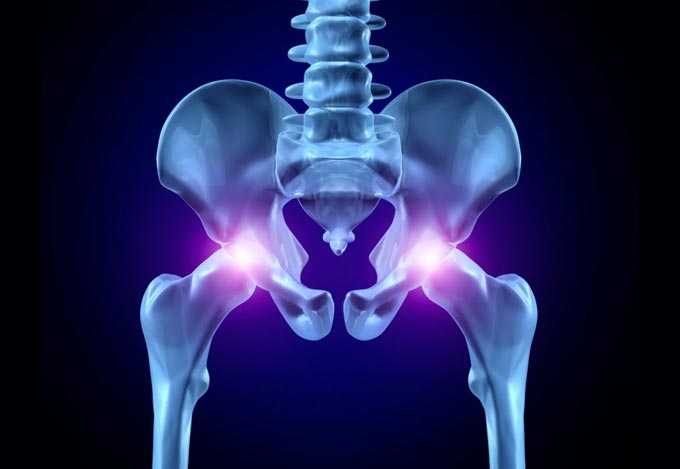

Έχει 5ετή μετεκπαίδευση και εργασία στο Ηνωμένο Βασίλειο ως ειδικός Ορθοπαιδικός Χειρουργός. Έχει εργαστεί στα Ορθοπαιδικά Τμήματα των Νοσοκομείων Southampton University Hospitals NHS Trust, Leeds Teaching Hospitals NHS Trust και στο Northampton General Hospital NHS Trust, με υποεξειδίκευση στη Χειρουργική Ώμου, Γόνατος, Ισχίου, Ποδοκνημικής & Άκρου Ποδός, Ώμου & Αγκώνος και Γενικού Τραύματος Ενηλίκων και Παίδων.

Κατά τη διάρκεια της εργασίας του στο Ηνωμένο Βασίλειο εκπαιδεύτηκε σε σύγχρονες τεχνικές Αρθροσκοπικής Χειρουργικής και Επανορθωτικής Χειρουργικής Ισχίου, Γόνατος και Ώμου. Επιπλέον έχει δώσει πολυάριθμες διαλέξεις και έχει εκπαιδεύσει νεότερους Ορθοπαιδικούς και φοιτητές Ιατρικής. Αξιοσημείωτο και πλούσιο είναι το επιστημονικό του έργο με συμμετοχή σε δεκάδες συνέδρια και σεμινάρια στην Ελλάδα και στο εξωτερικό και έχει πληθώρα προφορικών ανακοινώσεων και δημοσιεύσεων.